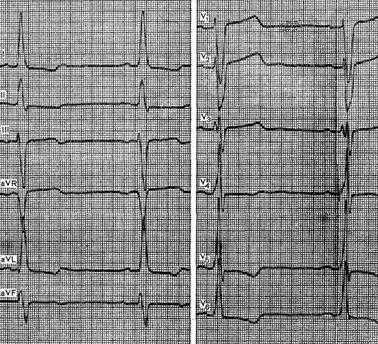

Рисунок. Гипертрофия правого желудочка

Типичные признаки выраженной гипертрофии левого желудочка с дистрофическими изменениями миокарда можно видеть на ЭКГ больного 63 лет с диагнозом: ревматический порок сердца, стеноз устья аорты. Отмечается отклонение электрической оси сердца влево до -15°, увеличение амплитуды зубца R в отведении V5 более 30 мм и зубца S в V1 более 25 мм. Зубец R в отведении V5 выше, чем в V4. Время внутреннего отклонения в левых грудных отведениях превышает 0,05 с. Отмечаются депрессия сегмента ST и инверсия зубца Т в отведениях I, aVL, V5 и V6, а также подъем сегмента ST в отведениях V1 и V2, Выявляются также признаки гипертрофии левого предсердия.

На рисунке представлена ЭКГ больного 28 лет с диагнозом: врожденный порок сердца, стеноз легочной артерии. На ЭКГ видны признаки гипертрофии правого желудочка первого типа: увеличение зубца R в отведении V1 до 20 см, смещение переходной зоны левее V6, отклонение электрической оси сердца вправо (A QRSII= +120°).

Примером гипертрофии обоих желудочков может служить приведенная на рисунке ЭКГ больной 28 лет с диагнозом, ревматический сочетанный порок сердца, возвратный ревмокардит, мерцательная аритмия, недостаточность кровообращения II степени. На ЭКГ видны признаки гипертрофии правого желудочка, в частности отклонение электрической оси сердца вправо, с поворотом вокруг продольной оси по часовой стрелке (синдром QIIISI), увеличение амплитуды и ширины зубца R в отведениях V1 и V2.

Кроме того, имеются указания на гипертрофию левого желудочка: увеличение амплитуды зубца R в отведении V5 более 25 мм, зубец R в отведениях V5и V6 выше, чем в V4. Имеются признаки диффузных изменений миокарда.